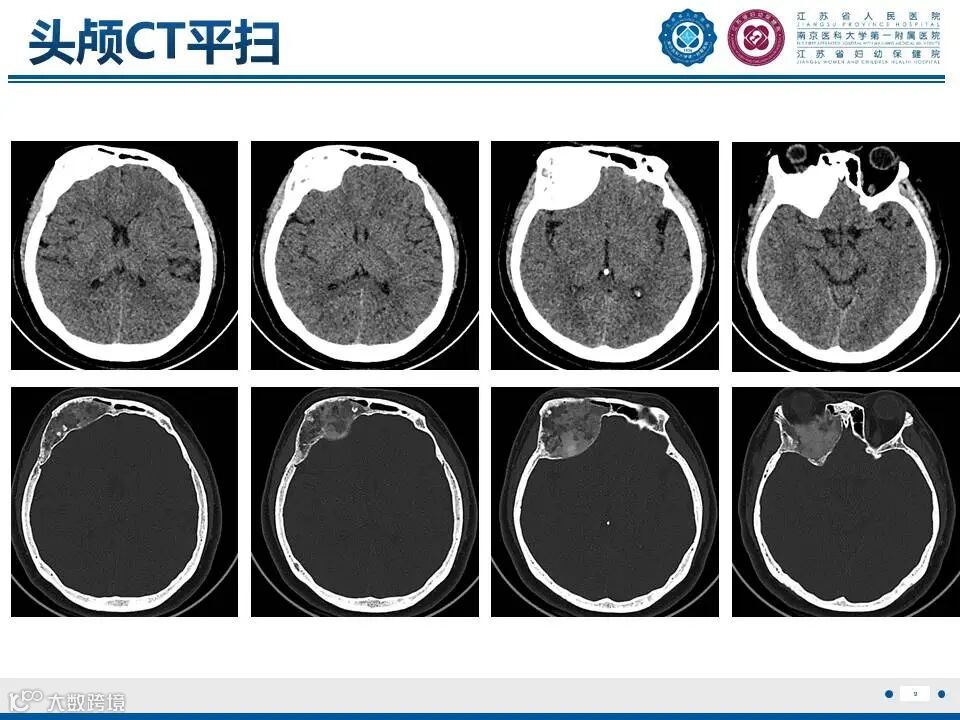

来源:江苏省人民医院放射科